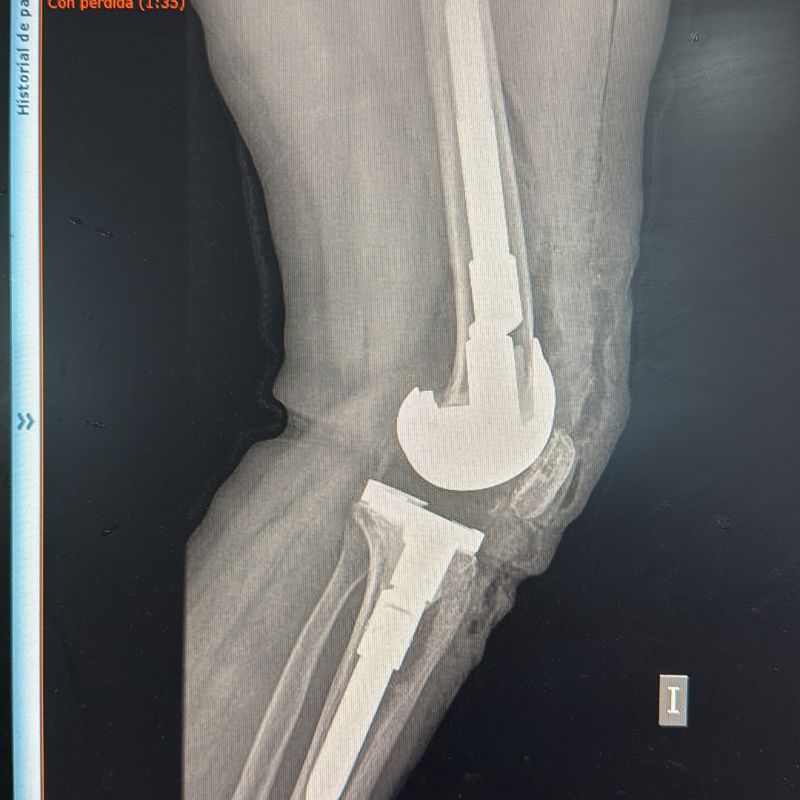

- Prótesis unicompartimentales de Rodilla.

- Prótesis Total de Rodilla.

- Retiro de Prótesis de Rodilla dolorosa o fallida.

- Prótesis de Revisión de Rodilla.